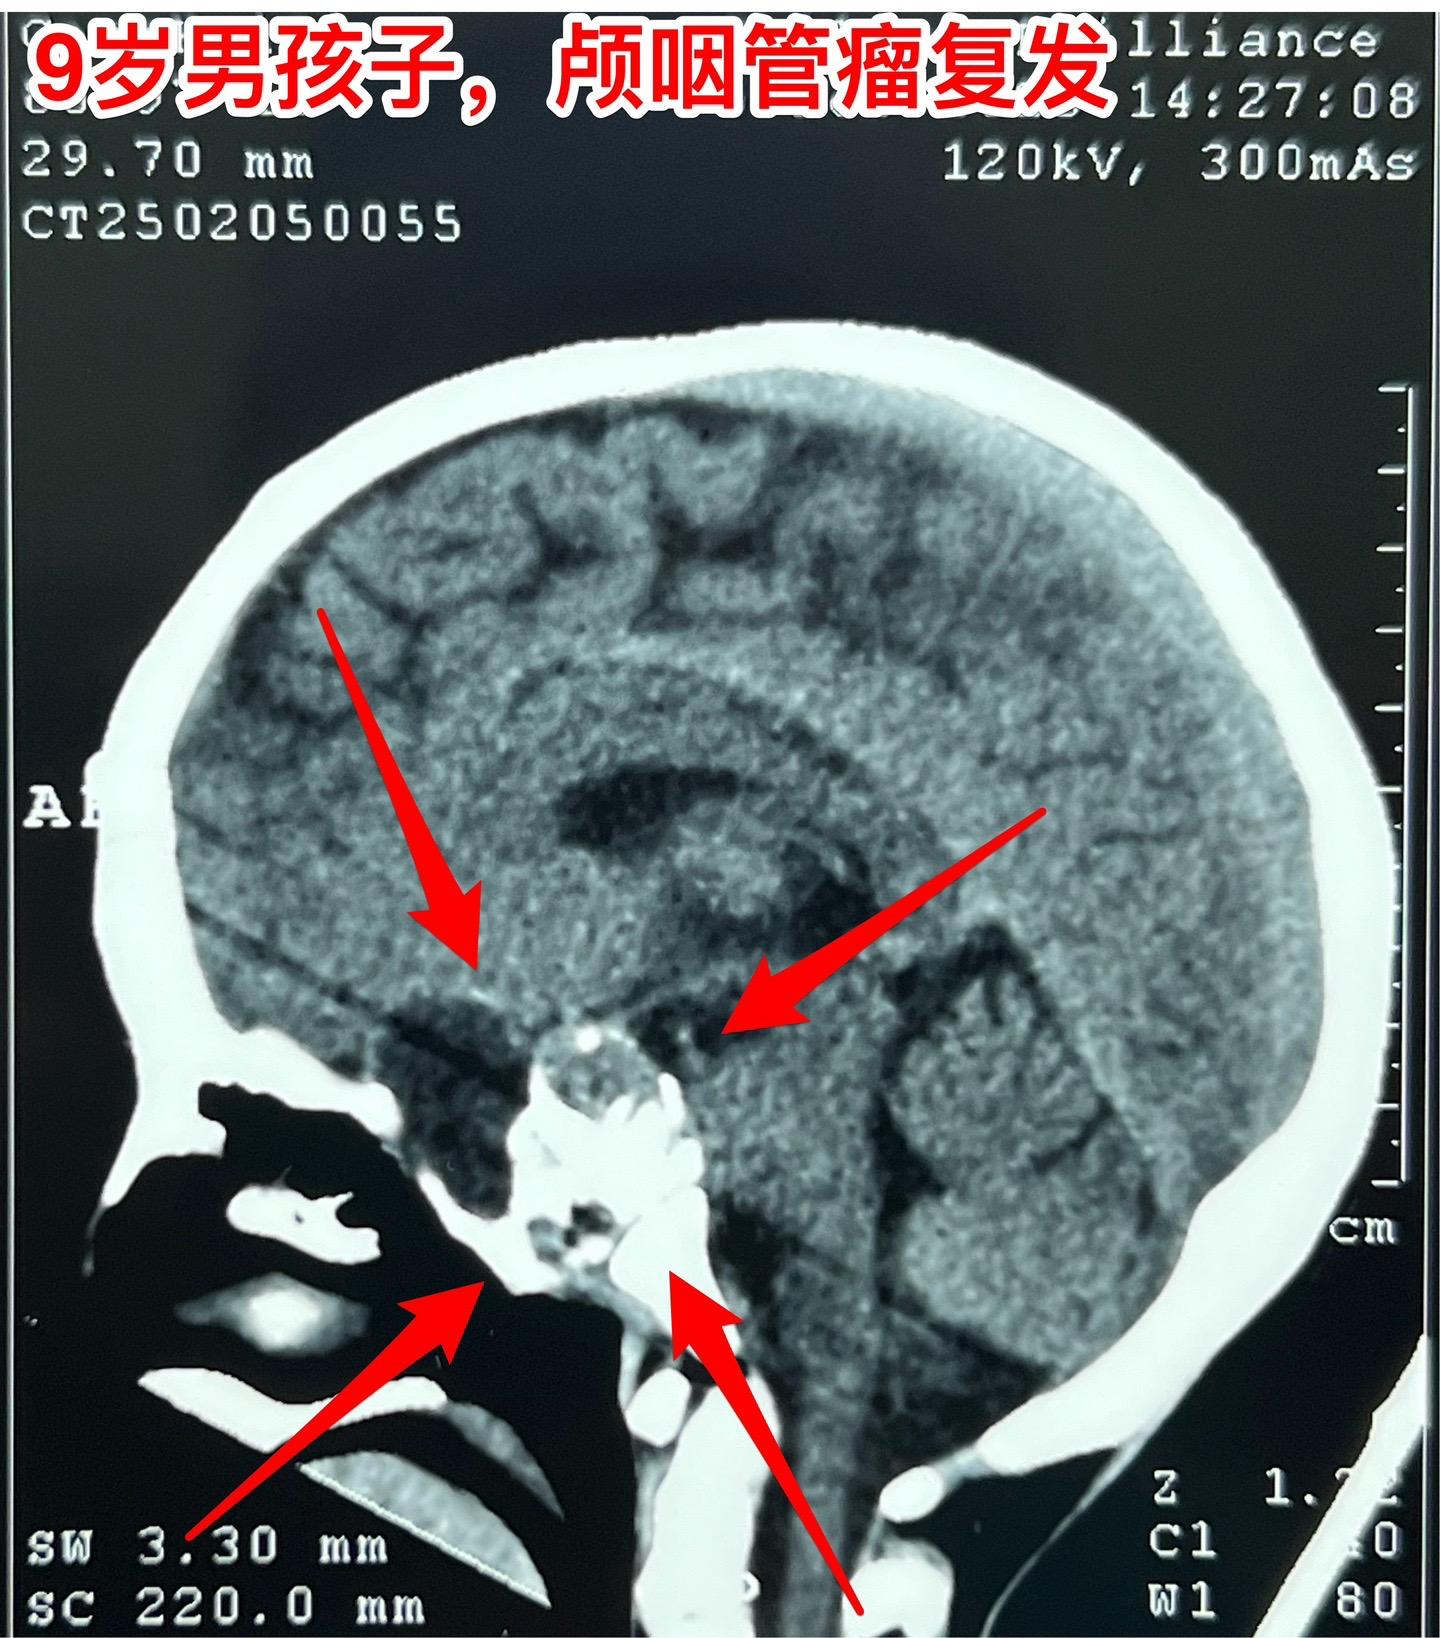

九岁男孩子颅咽管瘤复发,肿瘤生长快。南阳市男孩子2年半前曾经作了一次手术,2024年2月复查磁共振显示垂体窝内无肿瘤复发,鞍背骨质内有可疑异常信号。2025年1月复查磁共振即显示肿瘤复发而且直径达4厘米,患儿家长不敢相信肿瘤居然长得这么快!正月初八患儿即来住院,复查磁共振及CT见图。 病友们经常咨询的问题是肿瘤的生长速度。虽然颅咽管瘤是良性肿瘤,但是不能肯定地说颅咽管瘤的生长速度就很慢。即使在较长时间内肿瘤生长缓慢,也可能在某个时间段出现快速生长,也就是说颅咽管瘤的生长速度不是匀速的,难以预